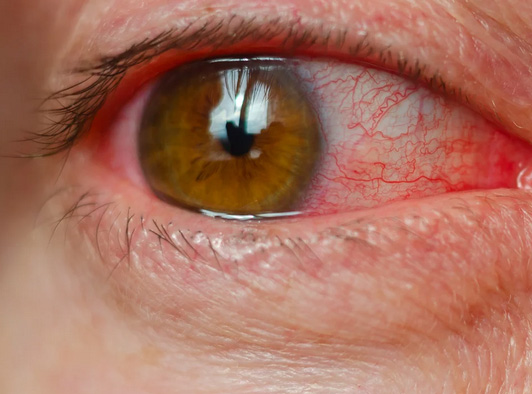

Conjuntivocálase: O que é essa Condição e como ela Afeta Seus Olhos?

A conjuntivocálase é o excesso da conjuntiva (a membrana que recobre o olho), que se torna flácida e enrugada, causando desconforto ocular.

Seus principais sintomas são olhos vermelhos, ardência, sensação de areia, lacrimejamento excessivo, visão instável e desconforto ao piscar ou usar lentes de contato.

O que é Conjuntivocálase?

É o nome dado ao excesso de conjuntiva (a membrana que recobre o olho), que se torna flácida e enrugada, causando desconforto ocular, lacrimejamento, ardência e até sensação de corpo estranho.

Quais são os sintomas da Conjuntivocálase?

- Olhos vermelhos com frequência

- Ardência ou queimação

- Sensação de areia nos olhos

- Lacrimejamento excessivo

- Visão oscilante

- Desconforto ao piscar ou ao usar lentes de contato